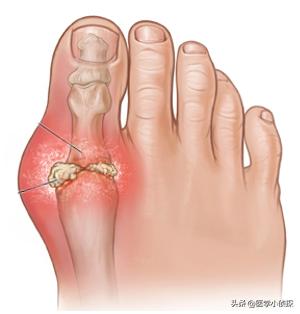

Il y a des nodules goutteux autour des articulations ou dans les perce-oreilles, et en cas de goutte de longue durée, les articulations sont atrophiées, déformées et souvent ulcérées, avec un écoulement crayeux des plaies.

On trouve des calculs de goutte sur le corps de presque toutes les personnes souffrant de goutte, et ils s'accumulent au fur et à mesure que la maladie évolue.fait des ravages dans les articulations de nos membres, entraînant des gonflements et des douleurs chroniques, des raideurs et des déformations, voire des fractures.

La manifestation la plus typique de la goutte est la formation de calculs goutteux dans les articulations, ce qui entraîne des déformations articulaires et des douleurs intenses.

II. découverte des calculs de la goutte

Le site typique des calculs goutteux sous-cutanés est le pavillon de l'oreille, généralement autour des articulations récurrentes, de l'épervier, du tendon d'Achille et de la bourse rotulienne. L'aspect des organismes sous-cutanés surélevés de couleur jaune-blanc-rougeâtre et de taille variable, la surface de la peau est fine, et une matière blanche poudreuse ou pâteuse s'écoule après rupture, qui ne guérit pas sur une longue période de temps. Les calculs goutteux sous-cutanés coexistent souvent avec l'arthrite goutteuse chronique. Les dépôts importants de calculs goutteux dans les articulations peuvent entraîner une destruction des os de l'articulation, une fibrose des tissus périarticulaires et des changements dégénératifs secondaires.

Les zones où les cristaux d'acide urique ont tendance à se déposer produisent des nodules durs de cristaux d'acide urique appelés nodules goutteux, souvent désignés sous le nom de calculs goutteux. Outre les articulations, les calculs goutteux peuvent également apparaître dans les zones où la température corporelle est basse, comme le lobe de l'oreille.

En outre, les cristaux d'urate se déposent dans le cartilage, la synovie, les tendons, les tissus mous et d'autres dépôts locaux du tissu sous-cutané, ce qui entraîne également la formation de calculs goutteux, dont la taille varie de quelques millimètres à plusieurs centimètres. La goutte peut alors évoluer d'une monoarthrite sporadique vers une polyarthrite récurrente, voire une arthrite persistante, des déformations articulaires et des cristaux d'urate. Les calculs de goutte peuvent entraîner une limitation significative des mouvements articulaires en affectant directement les articulations ou les tendons articulaires, et peuvent également entraîner des lésions osseuses et une incapacité fonctionnelle ainsi que des douleurs dans les articulations.